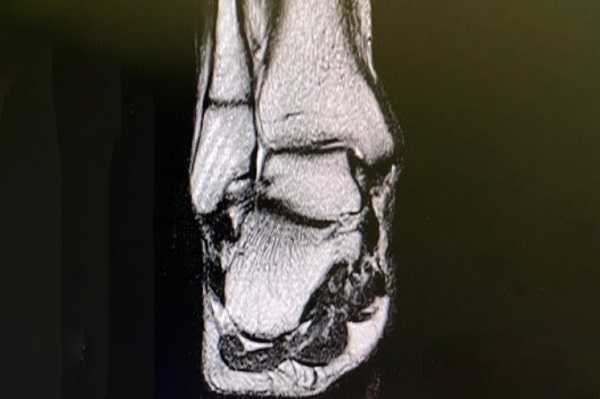

Рентгенограмма, МРТ после ампутации стопы

Метод обследования выбирает врач, учитывая диагноз, противопоказания. КТ предпочтительнее, если есть необходимость выявить изменения костной ткани: остеофиты, переломы, трещины, образование ложного сустава, аномалии развития, формы, строения костей, остеомиелит, опухоли костей голени и бедра, стопы. КТ может назначаться в случае наличия металлических элементов в теле, которые нельзя извлечь.